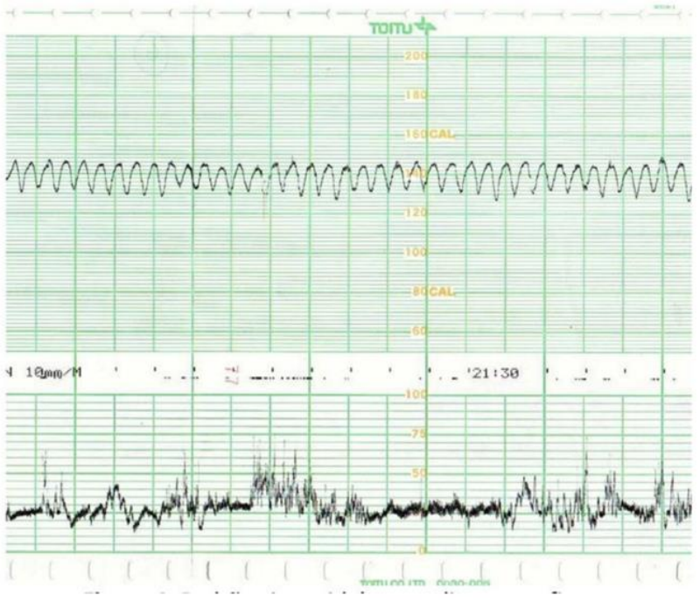

Sobre a cardiotocografia ante parto abaixo, pode-se afirmar: